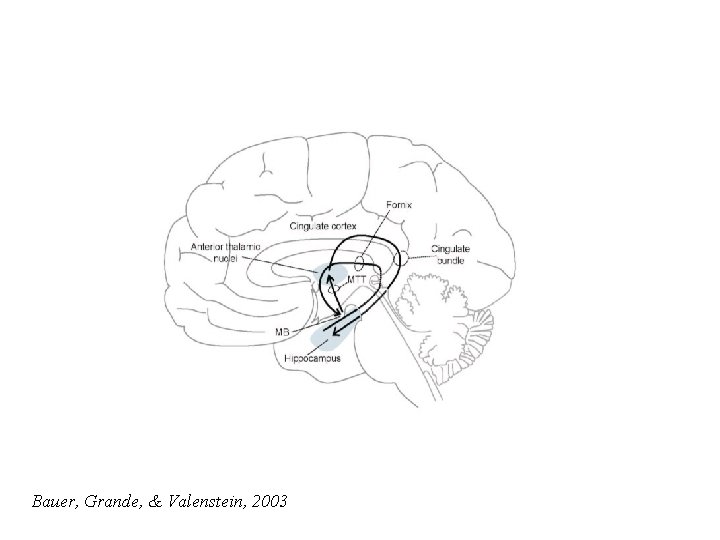

Bauer, Grande, & Valenstein, 2003

Two Limbic Circuits Anterior Thalamus Cingulate Gyrus Dorsomedial Thalamus Mamillothalamic Tract Mammilary Bodies Fornix Hippocampus Medial (Papez) Orbitofrontal Amygdalofugal pathways Uncus Amygdala Lateral

Two Limbic Circuits and the Two-system theory of amnesia Anterior Thalamus Cingulate Gyrus Dorsomedial Thalamus Mamillothalamic Tract Mammilary Bodies Orbitofrontal Amygdalofugal pathways Fornix Uncus Hippocampus Amygdala PRPH Medial (Papez) Lateral

Two Limbic Circuits and the Two-system theory of amnesia Anterior Thalamus Cingulate Gyrus Dorsomedial Thalamus Mamillothalamic Tract Mammilary Bodies Fornix Hippocampus Medial (Papez) Orbitofrontal Amygdalofugal pathways Uncus Amygdala Lateral

Two Limbic Circuits Anterior Thalamus Cingulate Gyrus Dorsomedial Thalamus Mamillothalamic Tract Mammilary Bodies Fornix Hippocampus Medial (Papez) Orbitofrontal Amygdalofugal pathways Uncus Amygdala Lateral

Two Limbic Circuits Anterior Thalamus Cingulate Gyrus Dorsomedial Thalamus Mamillothalamic Tract Mammilary Bodies Fornix Hippocampus Medial (Papez) Orbitofrontal Amygdalofugal pathways Uncus Amygdala Lateral Bauer, Grande, & Valenstein, 2003